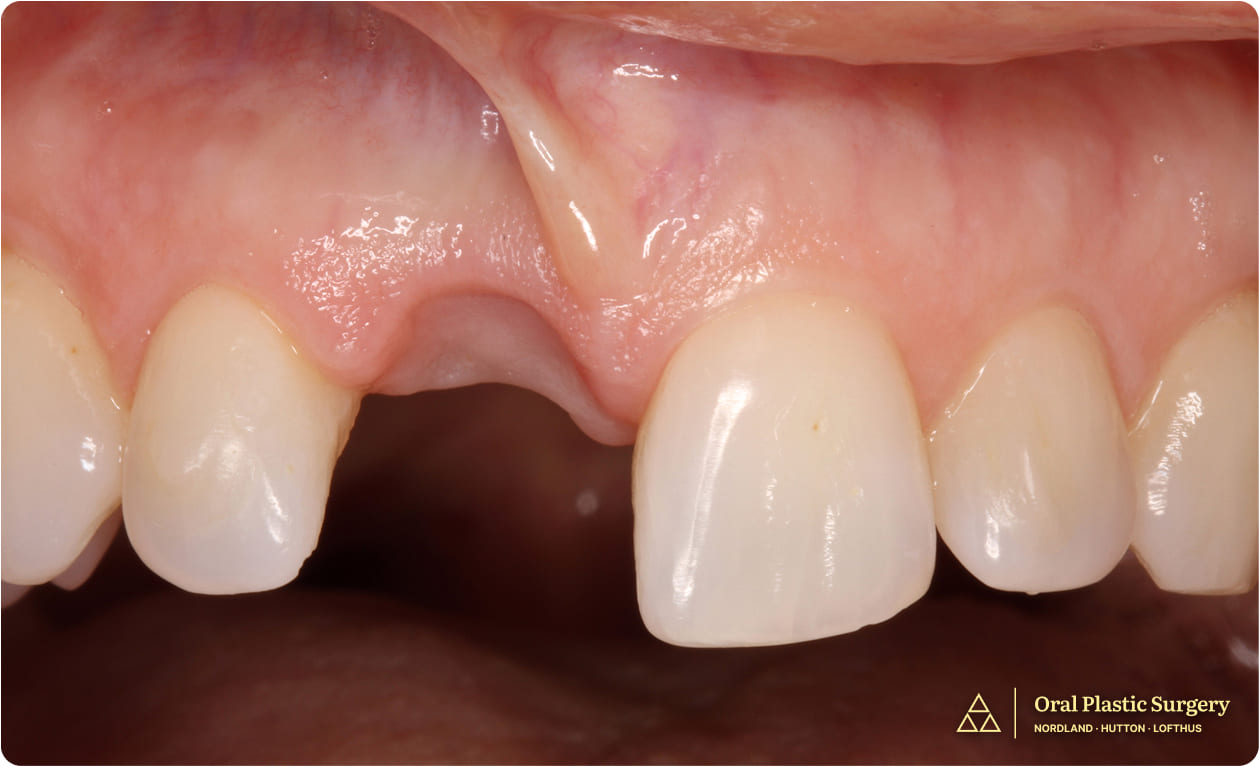

Pre-treatment frontal view showing spacing maintained with a removable prosthesis. The ridge deficiency is evident clinically, confirming CBCT findings of inadequate bone width for implant placement.